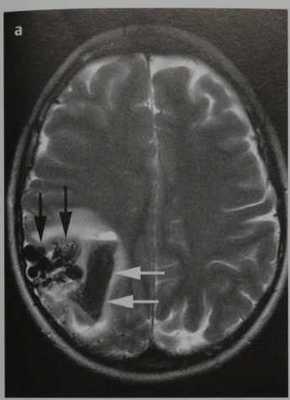

Пиальная артериовенозная мальформация головного мозга . МРТ, Т2-ВИ в аксиальной плоскости (а, b). ДСА в боковой проекции после введения КС в правую внутреннюю сонную артерию (с). Тубулярное отсутствие сигнала от потока в очаге АВМ (черные стрелки) на Т2-ВИ (а). Гипоинтенсивная гематома на Т2-ВИ (дезоксигемоглобин; а, белые стрелки).

Тубулярное отсутствие сигнала на поверхности головного мозга (вена; b, стрелка).

Определяется раннее контрастное усиление поверхностной мозговой вены, начинающейся от ветвей средней мозговой артерии (с, стрелка), и виден располагающийся между ними клубок сосудов (очаг, с)